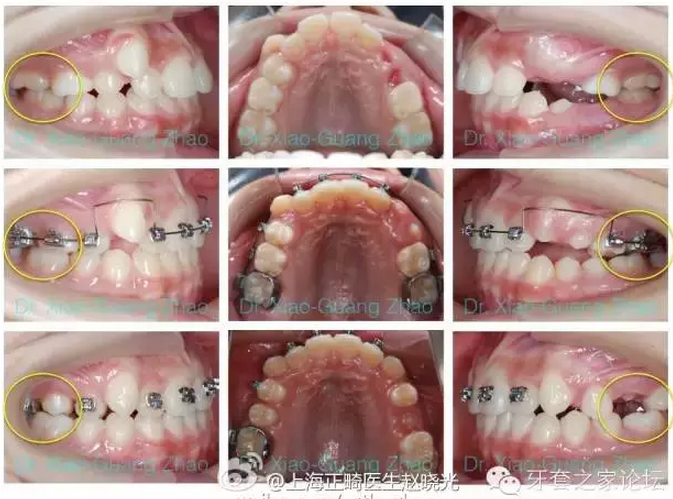

推磨牙向后一般是指推上頜磨牙向后,該技術(shù)在后牙咬合關(guān)系輕度錯(cuò)位,且上前牙存在輕度前突或輕中度擁擠的情況下使用。

如果能在上頜第二磨牙萌出之前開始治療,效果能夠更好。

(三)支抗種植釘結(jié)合固定矯治器。特點(diǎn)是不依賴患者配合,效果比較肯定,但是有一定的創(chuàng)傷性。